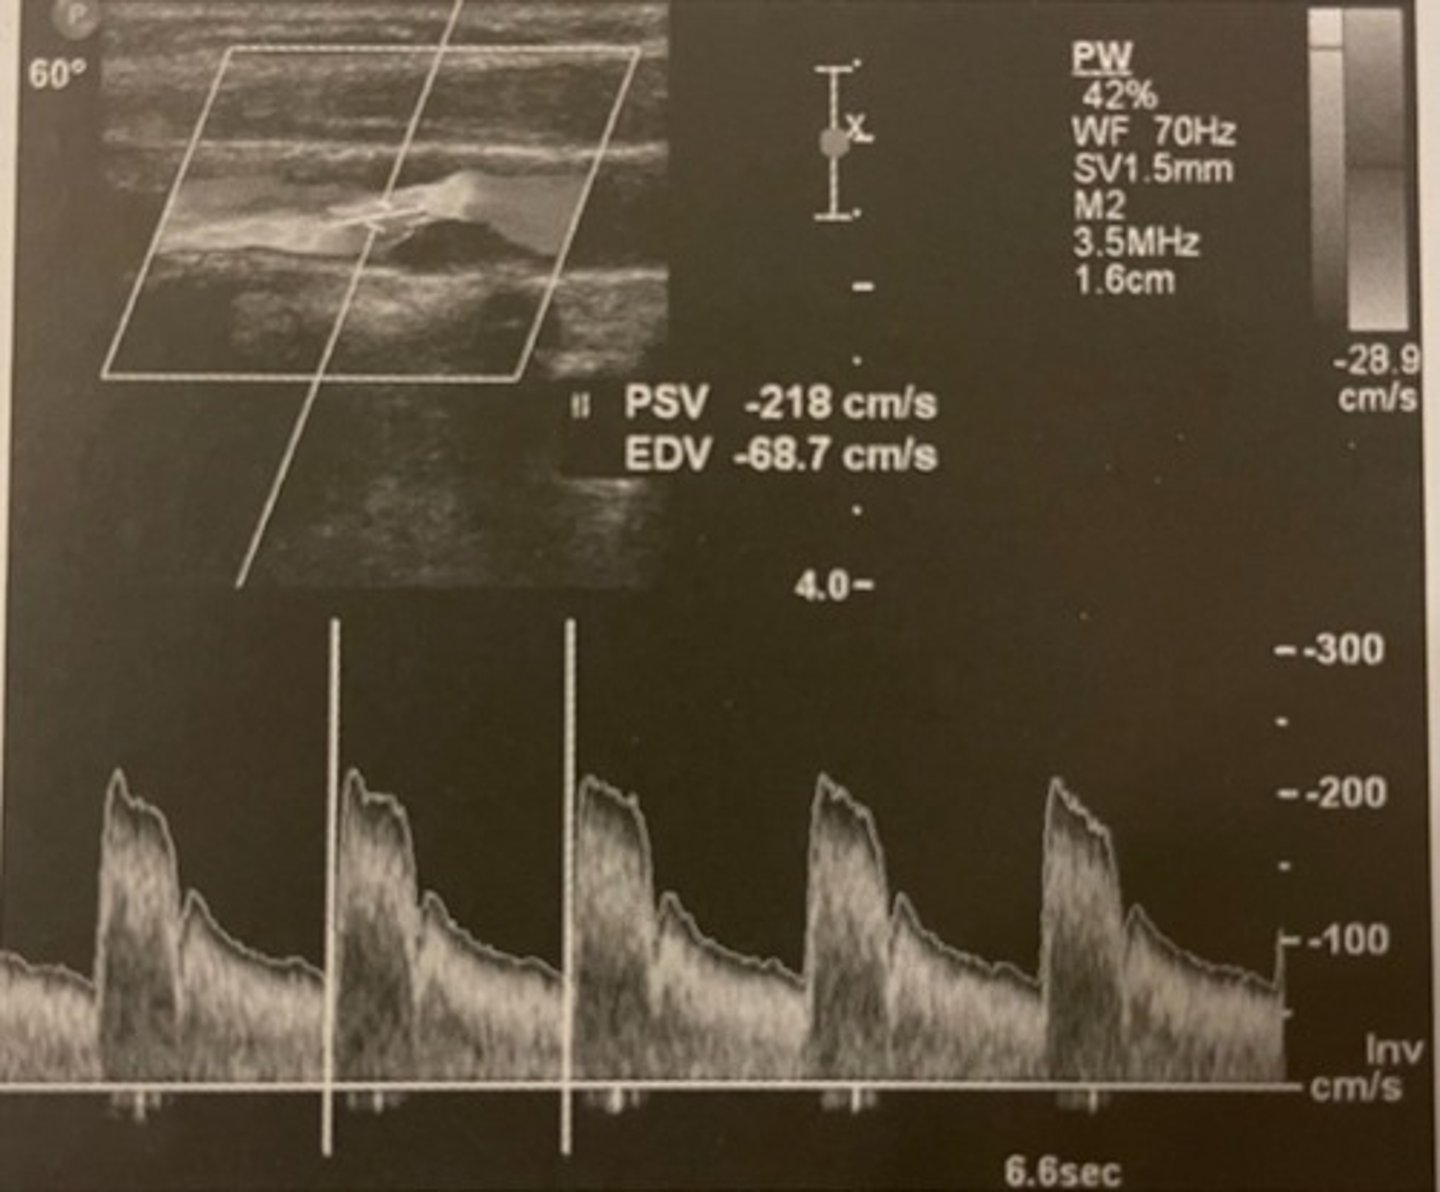

Sample was not obtained at maximum stenosis.

In this example, the ICA velocities may underestimate the category of stenosis. Why?

<p>In this example, the ICA velocities may underestimate the category of stenosis. Why?</p>